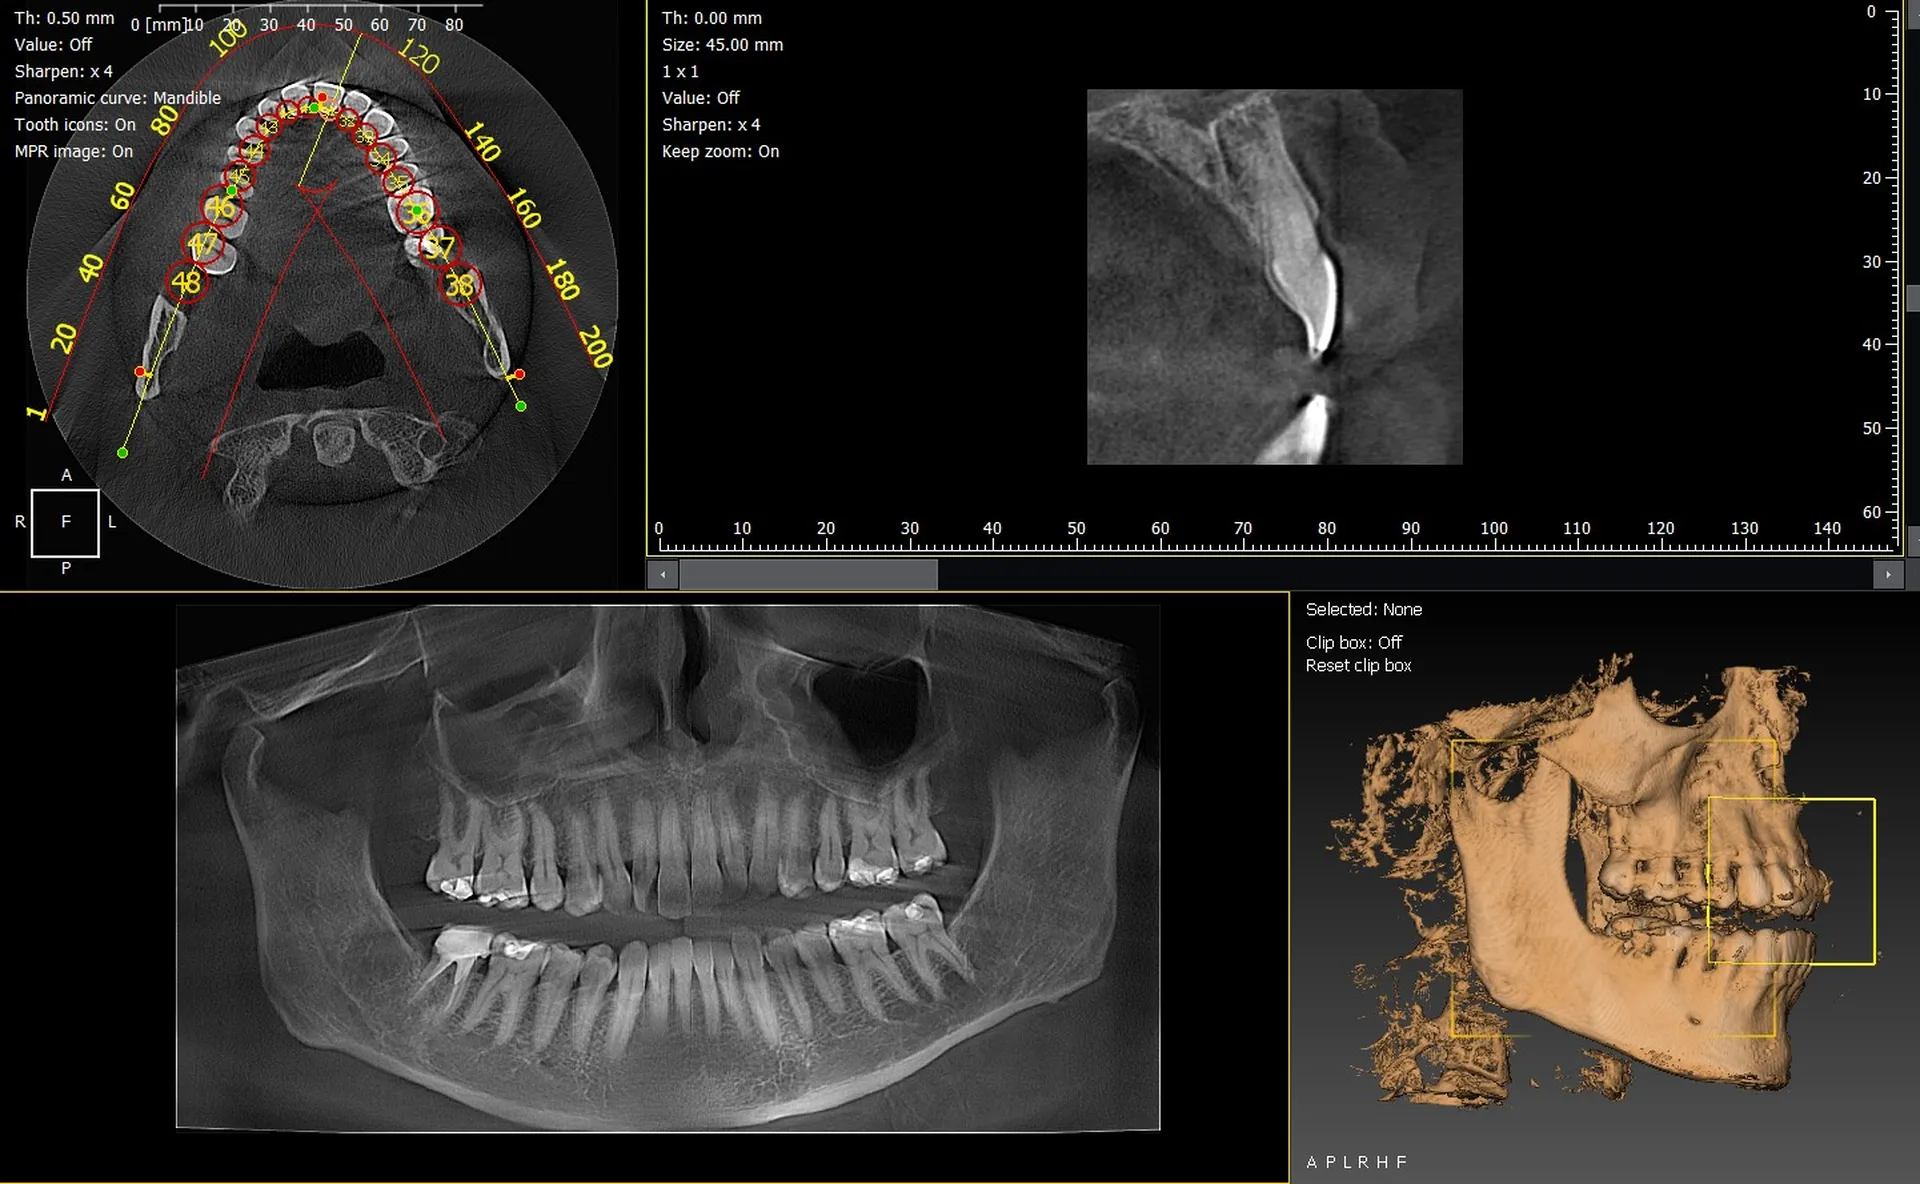

Les cabinets dentaires de La Ciotat et du département des Bouches-du-Rhône (13) modernisent leur plateau technique grâce à des équipements d’imagerie 3D performants et fiables. Les panoramiques CBCT 3D VistaVox de Dürr Dental et l’Owandy I-Max 3D font partie des solutions les plus avancées du marché, offrant une excellente qualité d’image et une précision diagnostique remarquable.

VistaVox 3D : précision et volume d’examen optimisé

Le VistaVox se démarque par :

• un volume d’examen parfaitement adapté à la forme de l’arcade,

• une haute résolution idéale pour l’implantologie et l’endodontie,

• une dose maîtrisée,

• un positionnement simple et rapide du patient.

Une solution parfaitement adaptée aux cabinets recherchant une imagerie 3D de grande précision dans le 13.

Owandy I-Max : compact, polyvalent et simple d’utilisation

L’Owandy I-Max 3D est particulièrement apprécié pour :

• son encombrement minimal, idéal pour les cabinets urbains,

• ses protocoles 2D/3D rapides,

• une excellente restitution des détails,

• une interface simple et intuitive.

Un choix stratégique pour les cabinets de La Ciotat souhaitant renforcer leur performance tout en optimisant l’espace.